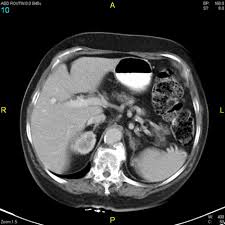

We had an appointment yesterday morning with the Oncologist to get the results of Nick's CT Scan. A few years ago Nick had a lump on his collar bone and after a biopsy they found he had Hodgkin's Lymphoma. He had another surgery to have some lymph nodes removed from under his arm pit and underwent a month of radiation therapy. Yesterday we found out that the scan was NEGATIVE (only in the medical field is negative a good thing) this means that Nick is 4 YEARS CANCER FREE!